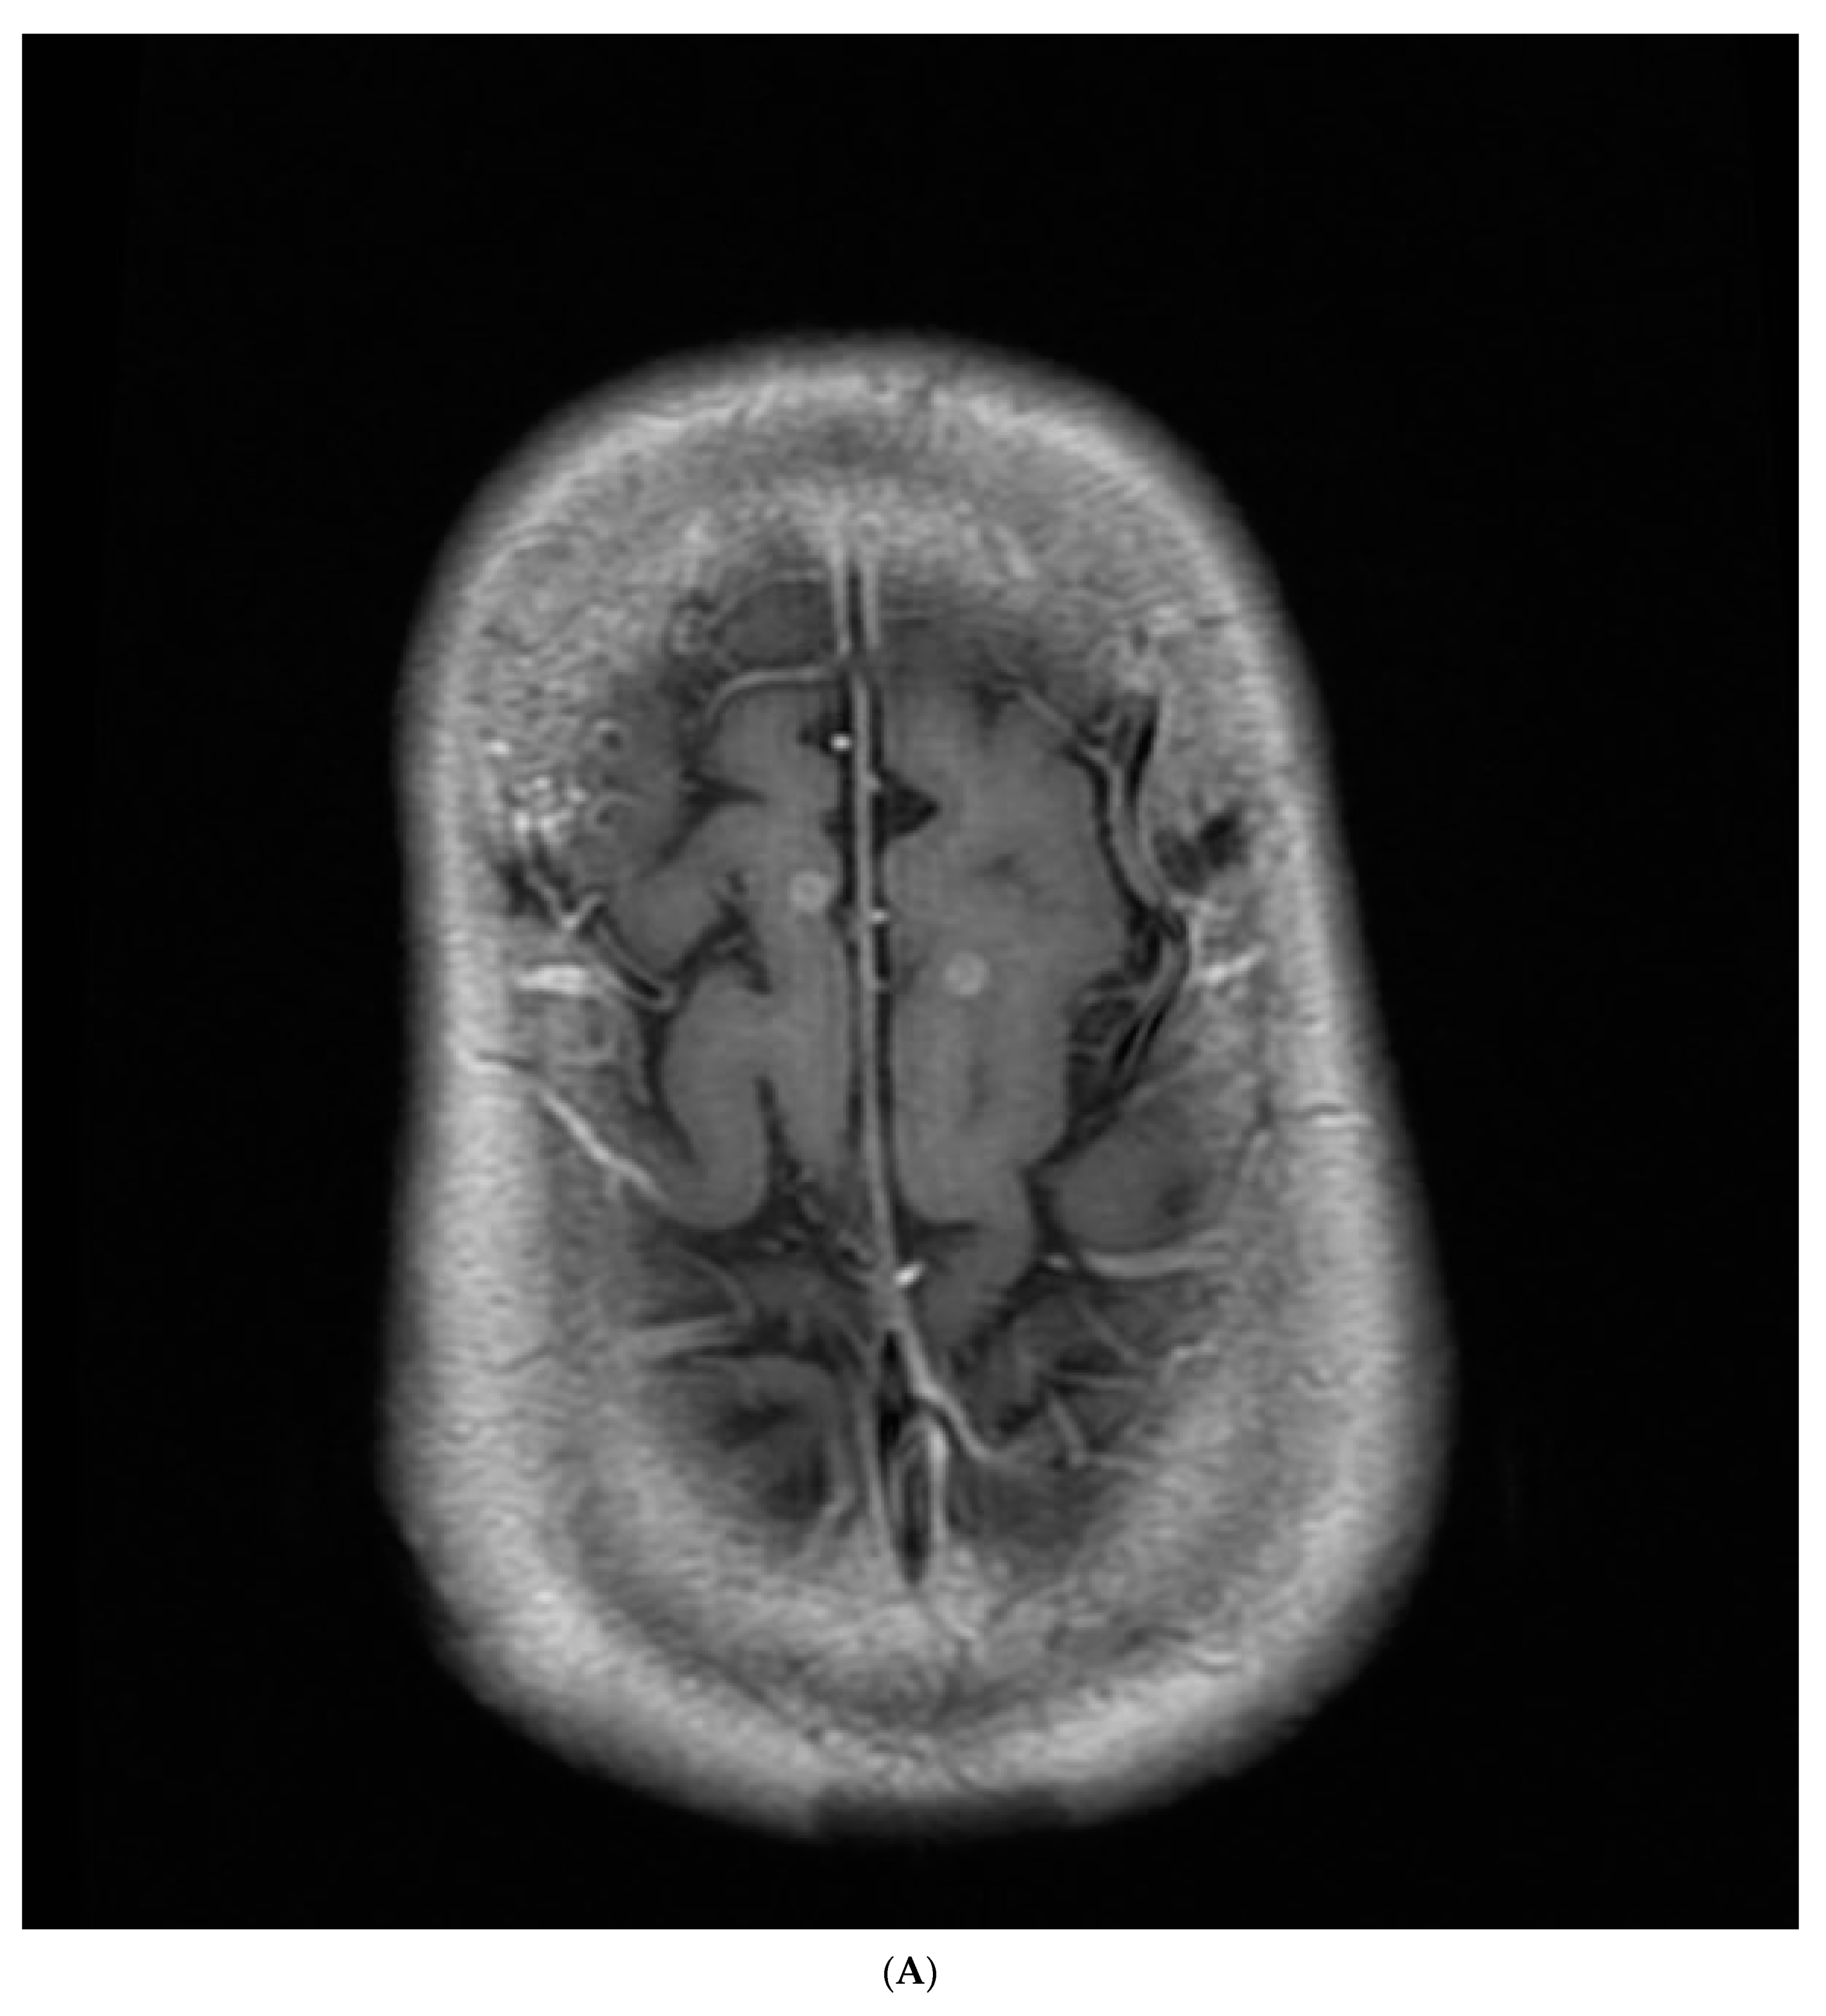

2. Case Report